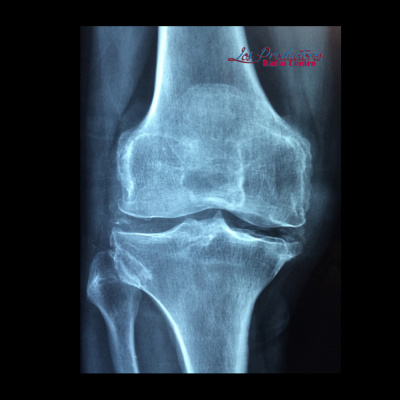

Platicamos con la Dra. Giselle Lozano Alcocer, Gineco-Obstetra y Médico Materno Fetal, con quien hablamos sobre Osteoporosis. Las fracturas osteoporóticas contribuyen a un deterioro en la calidad de vida, discapacidad, una mayor mortalidad y un alto costo económico en la atención ya que los cuidados debe empezar durante la infancia y continuar durante toda la vida, el tratamiento y cuidado de sus huesos. La Osteoporosis es una enfermedad del metabolismo del hueso que se caracteriza por la disminución de la masa ósea y deterioro de la arquitectura ósea, que conducen a la fragilidad del hueso con un consecuente incremento del riesgo de fracturas. Una de las armas que tenemos para prevenir esta enfermedad es el fortalecimiento óseo en edades tempranas, de esta manera el riesgo de padecer Osteoporosis en la adultez se reduce un 50%. La OMS ha catalogado a la osteoporosis como una de las epidemias de este siglo. Las fracturas osteoporóticas son la principal consecuencia de esta patología y es la causa de las